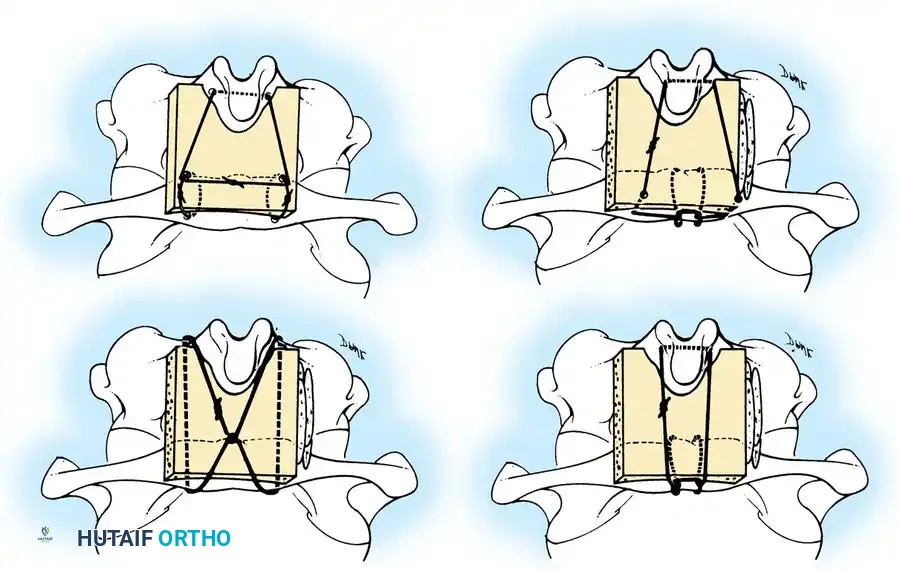

Posterior Cervical Fusion (PCF) and Instrumentation

Indications: Posterior tension band failure, irreducible facet dislocations requiring open reduction, or multi-level instability.

Surgical Steps:

1. Open Reduction: If a facet is dislocated, carefully lever the inferior articular process of the superior vertebra over the superior articular process of the inferior vertebra using a Penfield elevator.

2. Lateral Mass Screw Fixation:

* Utilize the Magerl or Roy-Camille trajectory.

* Magerl Technique: The entry point is 1 mm medial and 1 mm superior to the center of the lateral mass. The drill is angled 25 degrees laterally (to avoid the vertebral artery) and 15 degrees cephalad (to avoid the exiting nerve root).

3. Rod Contouring: Contour titanium or cobalt-chrome rods to match the patient's natural cervical lordosis and secure them to the screw heads with set screws.

4. Decortication and Fusion: Aggressively decorticate the lateral masses and facet joints with a high-speed burr. Pack the gutters with cancellous autograft (often harvested from the iliac crest) or high-quality allograft.